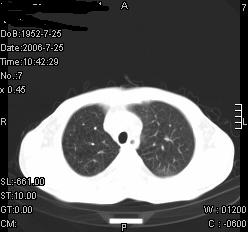

患者,男,54岁,咳嗦,咳痰20天。抗炎治疗2周。现esr76mm/h,目前患者症状明显好转,但发现两次ct片未见明显变化。两次分别做与7.25、7.31。第一次诊断右肺上叶炎症累计胸膜。大家看,从影像上内排除结核吗?

结核的可能性非常大,右上肺病变应该考虑干酪性肺炎。理由:

3.虽经抗炎治疗肺窗病灶有所吸收、减小,但纵隔窗病灶形态、密度、范围无明显变化。如果是单纯的大叶性肺炎,“抗炎治疗2周,目前患者症状明显好转”病灶应该基本消散了,至少也处于吸收消散期,密度变淡、范围变小。同时本病例所示其内的密度不均匀,见多发大小不一空洞样影也不符合大叶性肺炎吸收消散期表现。

病灶特点:片状 索条 结节混杂影,部分融合,密度不均,广泛累及相应胸膜.

临床治疗;二周未吸收.但症状好转.

多考虑:肺结核.